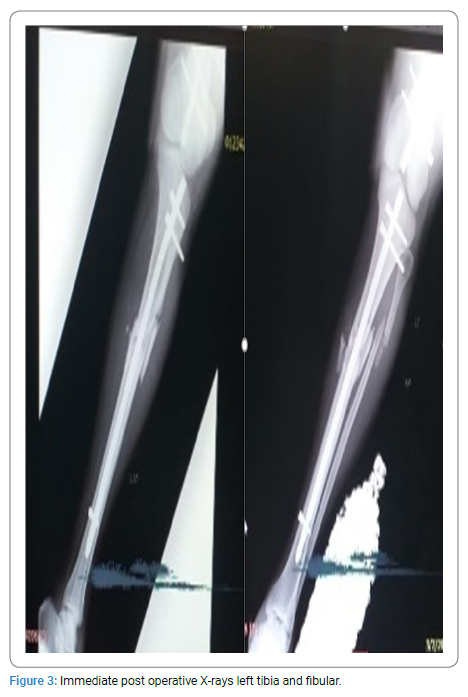

Retrograde intramedullary nailing (with stainless steel SIGN-Fin nails; (Figure 1,Figure 2) of the left and right femurs was done. The left tibia was nailed with a stainless-steel standard SIGN nail (Figure 3,Figure 4). The right femur, which was a closed fracture, was operated on first, then the left femur, and then the left tibia. All fractures were reduced open, avoiding the use of radiation. All fractures were reduced open, preventing the use of radiation.

Total surgery time was eighty-two (82) minutes with an estimated blood loss of 350 mLs. One unit of blood was given immediately post-surgery.

Surgery was Uneventful. Fetal heart Rate checked immediately post-surgery was 142 bpm and regular. No contractions were noticed.